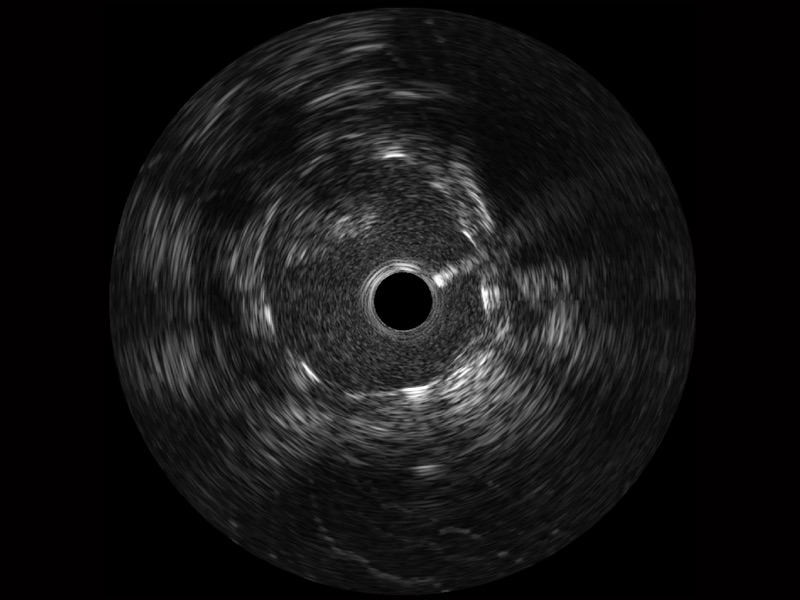

传统IVUS图像

对比传统IVUS导管成像,银河集团官网宽频IVUS图像的近场支架梁显影更细腻,远场中膜外血管仍清晰可辨,兼顾远中近,兼顾分辨力与穿透深度